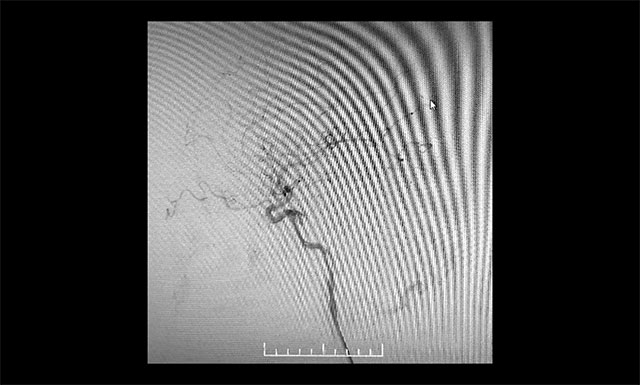

DSA 檢查顯示,左側(cè)天幕區(qū)硬腦膜動靜脈瘺,瘺口血流大,供血來源廣泛,引流靜脈有瘤樣擴(kuò)張。

DSA檢查顯示,左側(cè)天幕區(qū)硬腦膜動靜脈瘺

▲ DSA檢查顯示,左側(cè)天幕區(qū)硬腦膜動靜脈瘺